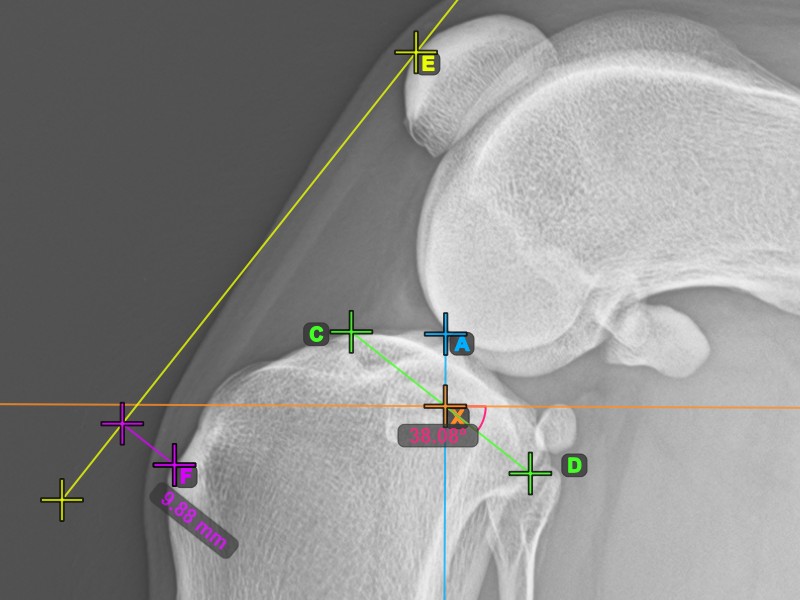

Um das TTA-Messverfahren abzuschließen, markieren Sie den hintersten Punkt der Crista Tibiae (Tuberositas Tibiae). Der Abstand zwischen der Tuberositas Tibiae und der Linie, die durch den vordersten Punkt der Patella verläuft, ist die erforderliche Anpassung für das TTA-Verfahren.

Das Bild unten zeigt die übliche Platzierung der Tibiatuberositas, des markantesten Punkts des Tibiakamms.